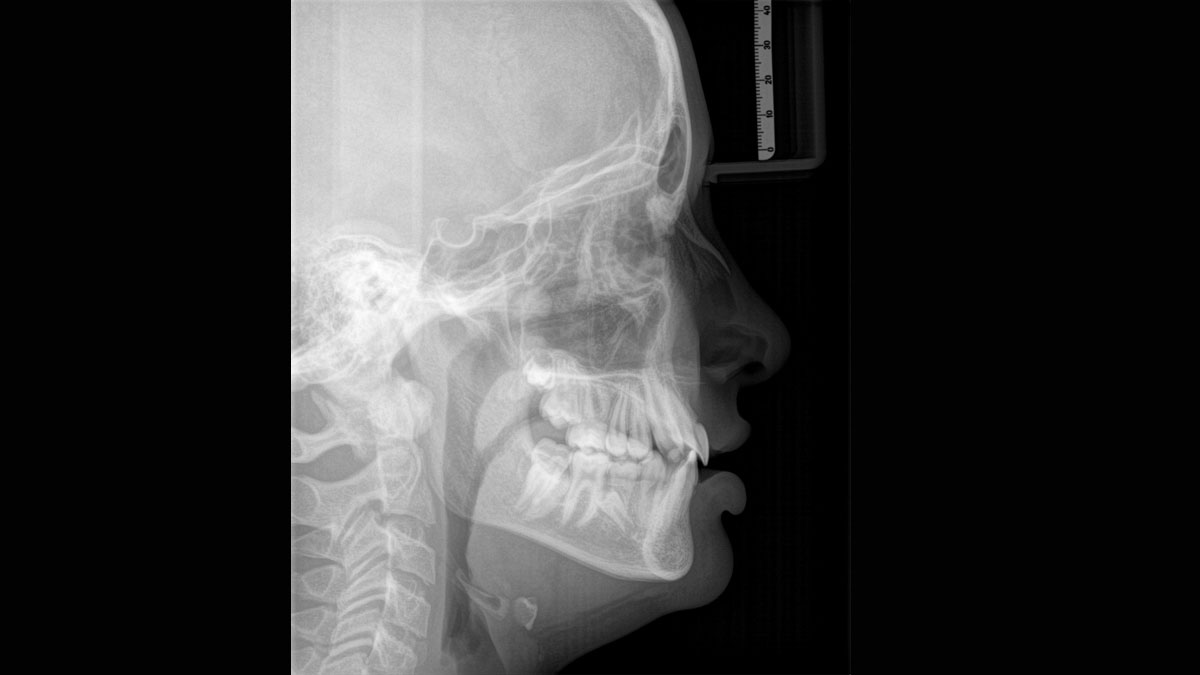

El brazo cefalométrico puede añadirse en el lado derecho o izquierdo de la unidad y solicitarse en el momento de la compra o instalarse en cualquier momento

El equipo de radiología 2D/3D de alta calidad con una amplia gama de servicios para cada clínica. Ya sea como un dispositivo puramente 2D o como un módulo 3D, el Orthophos S es un socio confiable y está optimizado para las tareas diarias. Su sensor CsI Plus con función de autofoco garantiza imágenes claras, incluso en casos anatómicamente difíciles. El posicionamiento automático del paciente junto con el bloque de mordida oclusal patentado permite un posicionamiento del paciente fácil y que ahorra tiempo. Para su uso en ortodoncia, la Orthophos S también está disponible con un brazo cefalométrico opcional. Y como para Dentsply Sirona es importante estar preparado para el futuro, el brazo cefalométrico se puede reacondicionar en cualquier momento.